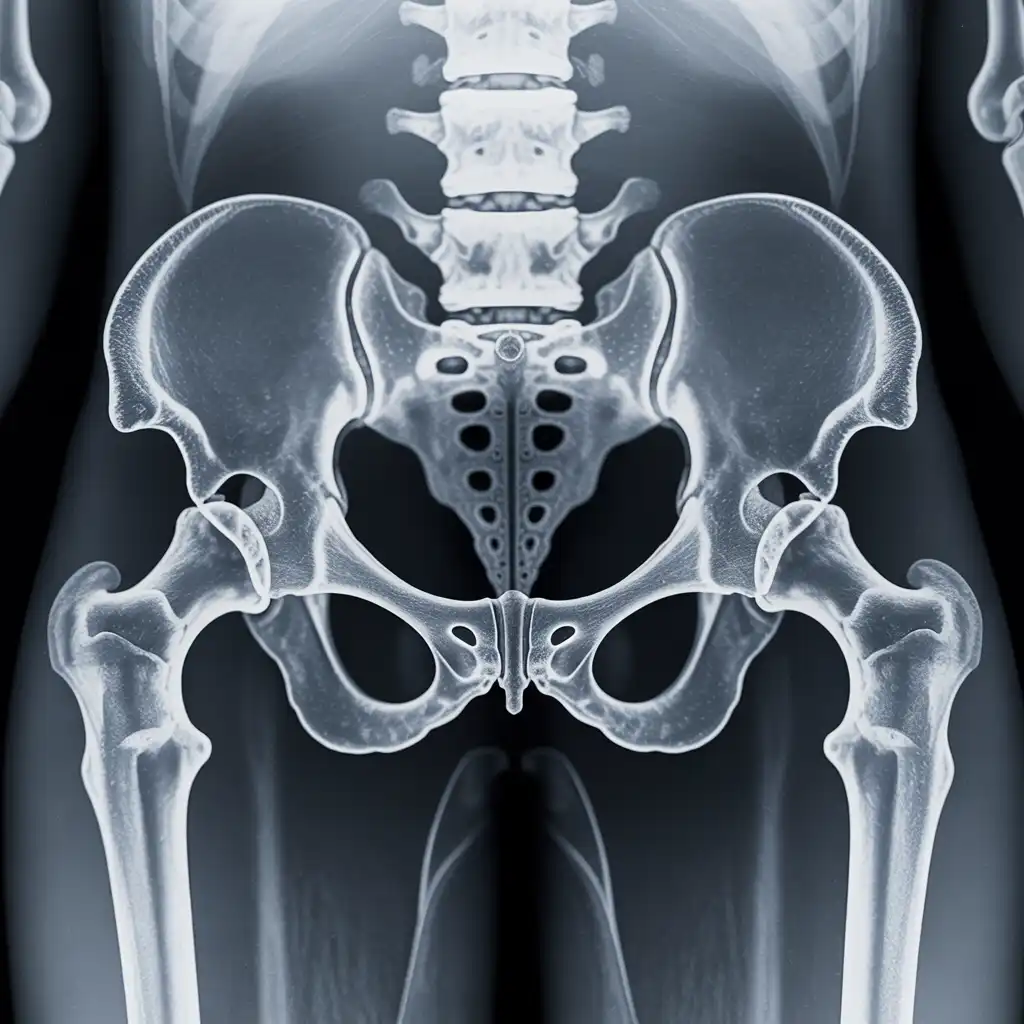

Una radiografia a domicilio è un esame radiologico eseguito da un tecnico specializzato che viene a casa tua con apparecchiature digitali portatili. L’esame si svolge sul posto, senza spostare il paziente e con la stessa qualità di una struttura ospedaliera.

Dopo l’acquisizione delle immagini, queste vengono inviate al medico radiologo che referta rapidamente e ti invia tutto in formato digitale. Un servizio comodo, sicuro e ideale per chi ha difficoltà negli spostamenti.